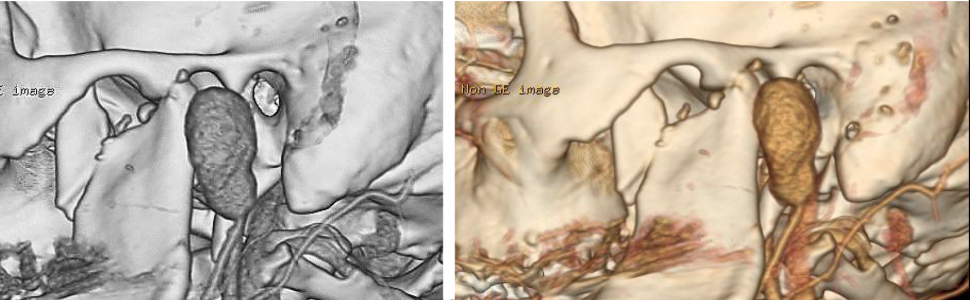

Przy przyjęciu stan ogólny chorego był dobry. Klinicznie widoczna była asymetria twarzy spowodowana obrzękiem okolicy przedusznej po stronie lewej. Rana powłok skórnych o długości około 2 cm zaopatrzona szwami. Poza tym powłoki skórne były niezmienione, bez cech stanu zapalnego. Przy palpacji wyczuwalne było wzmożone napięcie tej okolicy i tętnienie. Poza tym w badaniu klinicznym bez odchyleń od normy. Ze względu na wywiad, badanie kliniczne oraz brak możliwości obrazowania tętniaka w rutynowym badaniu TK wykonano badanie ultrasonograficzne, a następnie angiografię tomografii komputerowej, która uwidoczniła obecność tętniaka rzekomego o wymiarach 31 x 20 x 21 mm zlokalizowanego na poziomie odejścia tętnicy szczękowej od tętnicy szyjnej zewnętrznej lewej (ryc. 2).

Ryc. 2. Angiografia tomografii komputerowej – widoczny tętniak rzekomy, złamanie wyrostka kłykciowego i dziobiastego żuchwy po stronie lewej.

Kontrolna arteriografia potwierdziła zamknięcie naczynia, następnie nieznacznie wycofano cewnik i w ten sam sposób zamknięto światło tętnicy szyjnej zewnętrznej (ryc. 4).

Ryc. 4. Embolizacja tętnicy szyjnej zewnętrznej. Brak przepływu krwi w tętniaku.